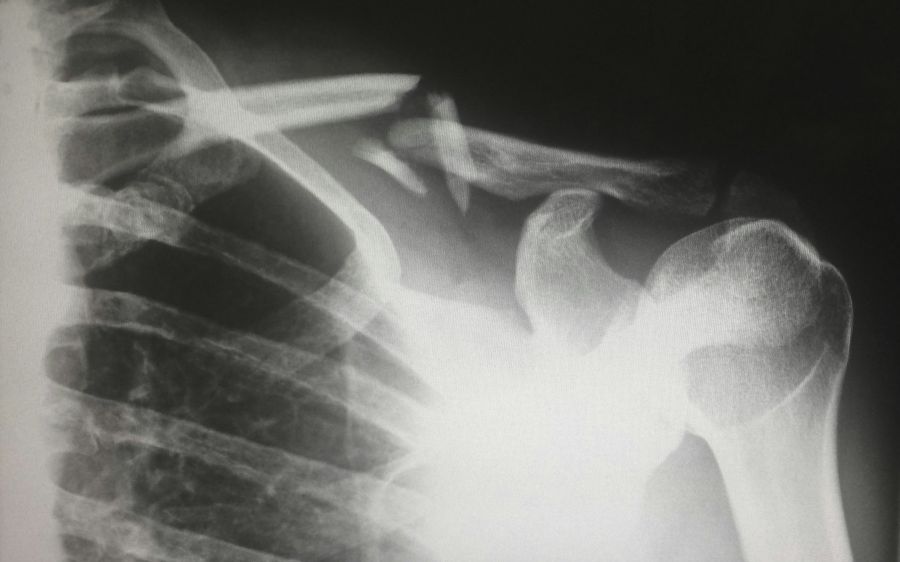

Long-term Outcomes of Biological Reconstruction for Primary Bone Sarcoma of the Humerus

Cancer diagnosis & Prognosis, 2025

This study assessed outcomes of biological reconstruction after humeral bone sarcoma resection in 23 patients. Four reconstruction techniques were used, primarily involving vascularized and non-vascularized fibular grafts. Despite complications such as graft fractures, non-union, and peroneal nerve palsy, oncological outcomes were favourable, with 22 of 23 patients surviving and good functional results (mean MSTS score: 78.9%). The study concludes that biological reconstruction is complex but offers effective oncological control and functional preservation.